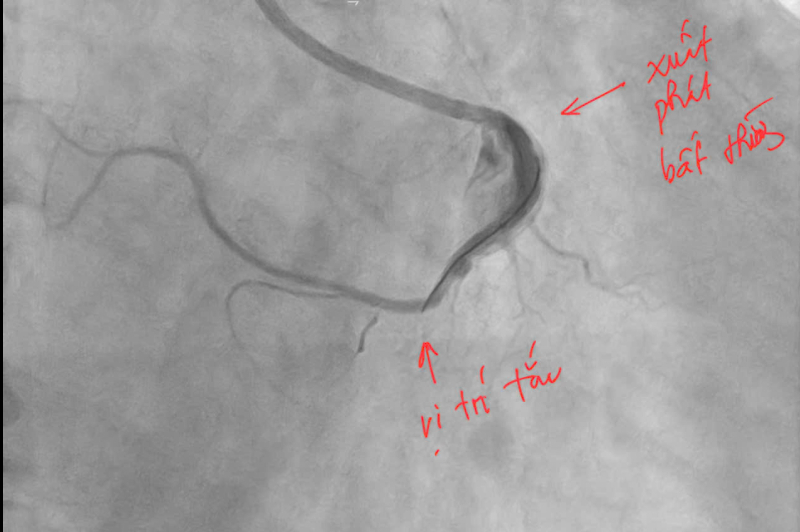

Hình ảnh trước khi can thiệp.

Ngay lập tức, bệnh nhân được kích hoạt quy trình cấp cứu tim mạch và chuyển đến phòng can thiệp mạch vành khẩn cấp. Kết quả chụp mạch vành cho thấy, bệnh nhân bị tắc hoàn toàn động mạch vành phải đoạn 2. Đáng chú ý, động mạch vành phải của người bệnh có vị trí xuất phát bất thường từ xoang vành trái của động mạch chủ – một dạng dị dạng hiếm gặp khiến việc tiếp cận và can thiệp trở nên phức tạp hơn nhiều so với các trường hợp thông thường.